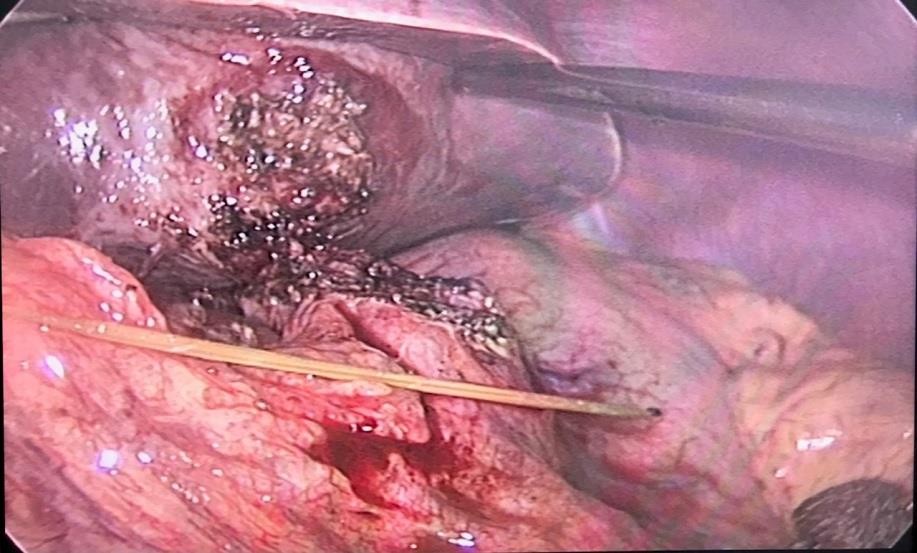

Một số hình ảnh ghi nhận trong và sau mổ:

Hình 2: Khối viêm dính mặt dưới gan trái, mạc nối nhỏ và thân tụy

Hình 3. Khối viêm dính được tiến hành phẫu tích

Hình 4: Đầu tăm được phát hiện trong quá trình phẫu tích

Hình 5: Cây tăm tre được rút ra khỏi gan trái

Bệnh nhân được hội chẩn và được chỉ định nhập viện Khoa Ngoại Tiêu Hóa để được tiếp tục theo dõi và điều trị. Sau 3 ngày điều trị, tình trạng đau bụng bệnh nhân tăng nhiều hơn, thăm khám ấn vào vùng thượng vị cho thấy tình trạng đau tăng hơn nhiều, kèm cảm ứng phúc mạc (+) nên bệnh nhân đã được chỉ định mổ cấp cứu bằng phẫu thuật nội soi vào tối cùng ngày. Kết quả phẫu thuật cho thấy mặt dưới gan trái tạo thành khối viêm dính kích thước 30x20mm, phẫu thuật viên đã tiến hành phẫu tích và lấy ra 1 chiếc tăm tre dài 70mm xuyên thủng vào trong gan trái, kiểm tra dạ dày không phát hiện lổ thủng, các tạng khác không thấy tổn thương. Sau phẫu thuật 2 ngày, bệnh nhân ổn định, bụng mềm, vết mổ khô, ăn uống được, trung đại tiện bình thường. Dự kiến sẽ cho ra viện trong vài ngày tới.